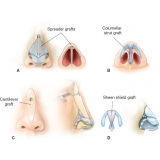

Conheça os procedimentos de excelência para a realização de uma cirurgia plástica a laser!